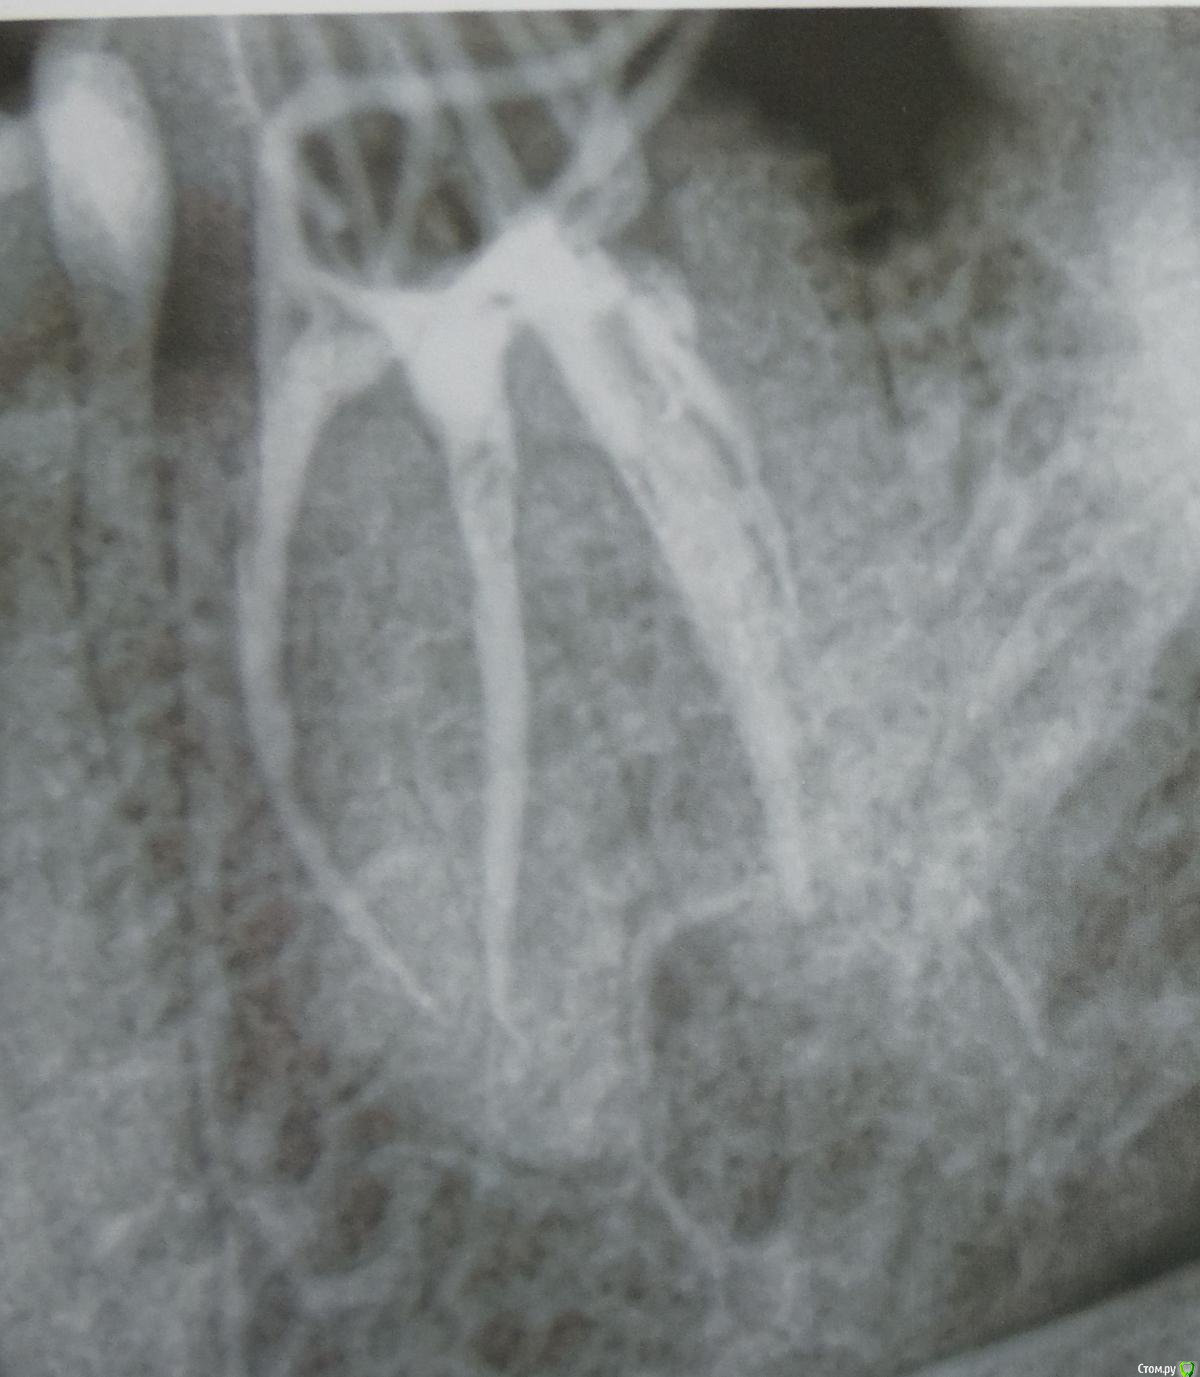

Антон999 Опубликовано 21 ноября, 2017 Поделиться Опубликовано 21 ноября, 2017 Здравствуйте, у меня был контактный кариес на нижней шестерке, зуб депульпировали, штифт не ставили, запломбировали свыше ½ зуба композитом светового отверждения, через неделю произошел маленький скол пломбы в районе контактного пункта, я пришел, мне запломбировали полость скола световой пломбой, но при первом же приеме пищи, эта маленькая пломба отвалилась от большой, я обратился еще раз и мне высверлили часть пломбы (но не всю) и уже большим куском налепили пломбу на пломбу, но теперь у меня не плотный контактный пункт, попадает пища, и под эту “вторую” пломбу заходит зубная нить (фото) и пища попадает под пломбу, с помощью объемной нити вычищаю под ней, но мне кажется она со временем отвалиться. Скажите пожалуйста нужно ли мне опять все переделывать? Допустимо ли удалять часть пломбы, а не всю, и крепить новую? В коронковой части зуба, только половина своих стенок, нечего страшного, что штифтом не укрепили? И заодно посмотрите пожалуйста качественно ли мне запломбировали три канала в этом зубе, спасибо. Ссылка на комментарий

red_butler Опубликовано 21 ноября, 2017 Поделиться Опубликовано 21 ноября, 2017 Зуб нужно протезировать искусственной коронкой, каналы нормально пломбированы. 1 Ссылка на комментарий

igorstom Опубликовано 24 ноября, 2017 Поделиться Опубликовано 24 ноября, 2017 В Вашем случае, где разрушение зуба более 50% показано не терапевтическое восстановление зуба пломбировочным материалом, а ортопедическое лечение, то есть протезирование (внутрикорневая вкладка, коронка). Пломбы показаны при достаточно выраженных стенках своего зуба. К сожалению таких стенок у Вас не наблюдается.Штифты не спасают пломбы от сколов, более того, они играют роль клина, что наоборот даже способствует сколам и расколам пломб.Добавлять пломбу допускается при состоятельности предыдущей.По каналам особых проблем не заметил.Есть ещё ряд замечаний. Но они больше профессиональные. Поэтому промолчу. 1 Ссылка на комментарий